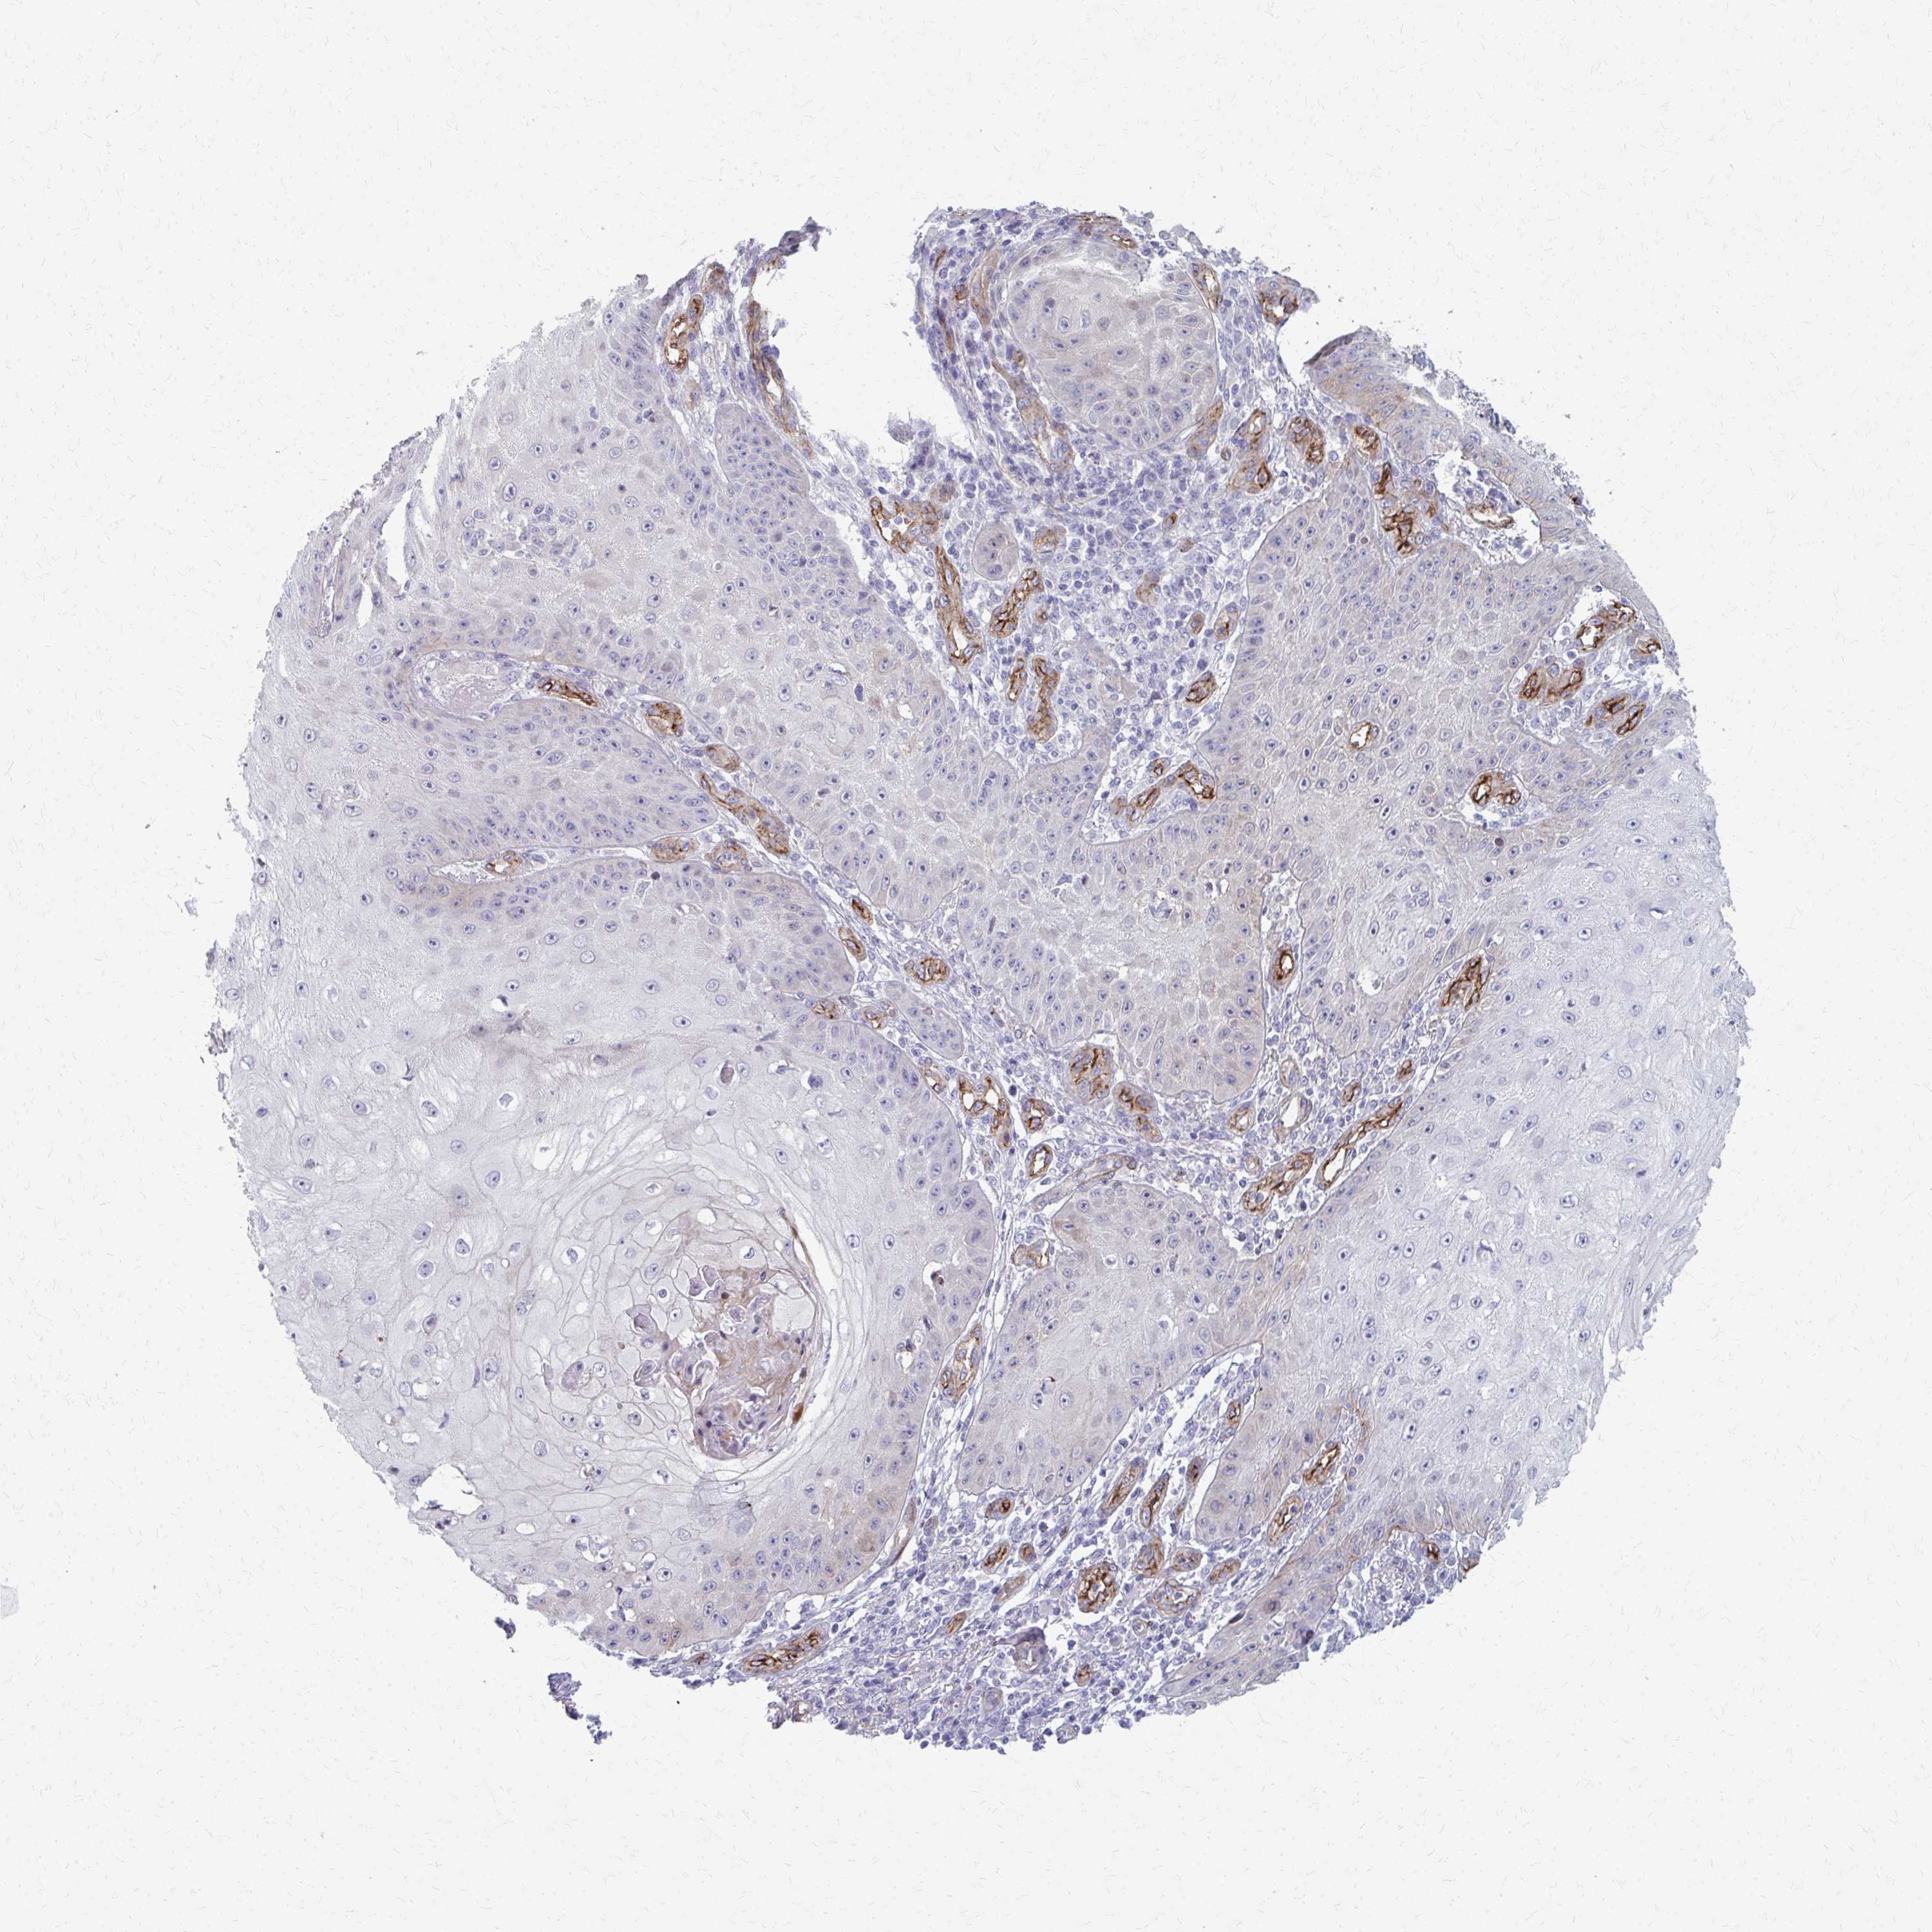

SKIN CANCER - Protein expressioni

A mouse-over function shows sample information and annotation data. Click on an image to view it in a full screen mode. Samples can be filtered based on level of antibody staining by selecting one or several of the following categories: high, medium, low and not detected. The assay and annotation is described here.

Antibody stainingi

Antibody staining in the annotated cell types in the current human tissue is reported as not detected, low, medium, or high, based on conventional immunohistochemistry profiling in selected tissues. This score is based on the combination of the staining intensity and fraction of stained cells.

Each image is clickable and will lead to virtual microscopy that enables deeper exploration of all samples and also displays staining intensity scores, fraction scores and subcellular localization as well as patient and tissue information for each sample.

Antibody HPA051767

Antibody CAB046467

Staining

High

Medium

Low

Not detected

Intensity

Strong

Moderate

Weak

Negative

Quantity

>75%

75%-25%

<25%

None

Location

Nuclear

Cytoplasmic/membranous

Cytoplasmic/membranous,nuclear

Basal cell carcinoma

Squamous cell carcinoma, NOS

Squamous cell carcinoma, metastatic, NOS